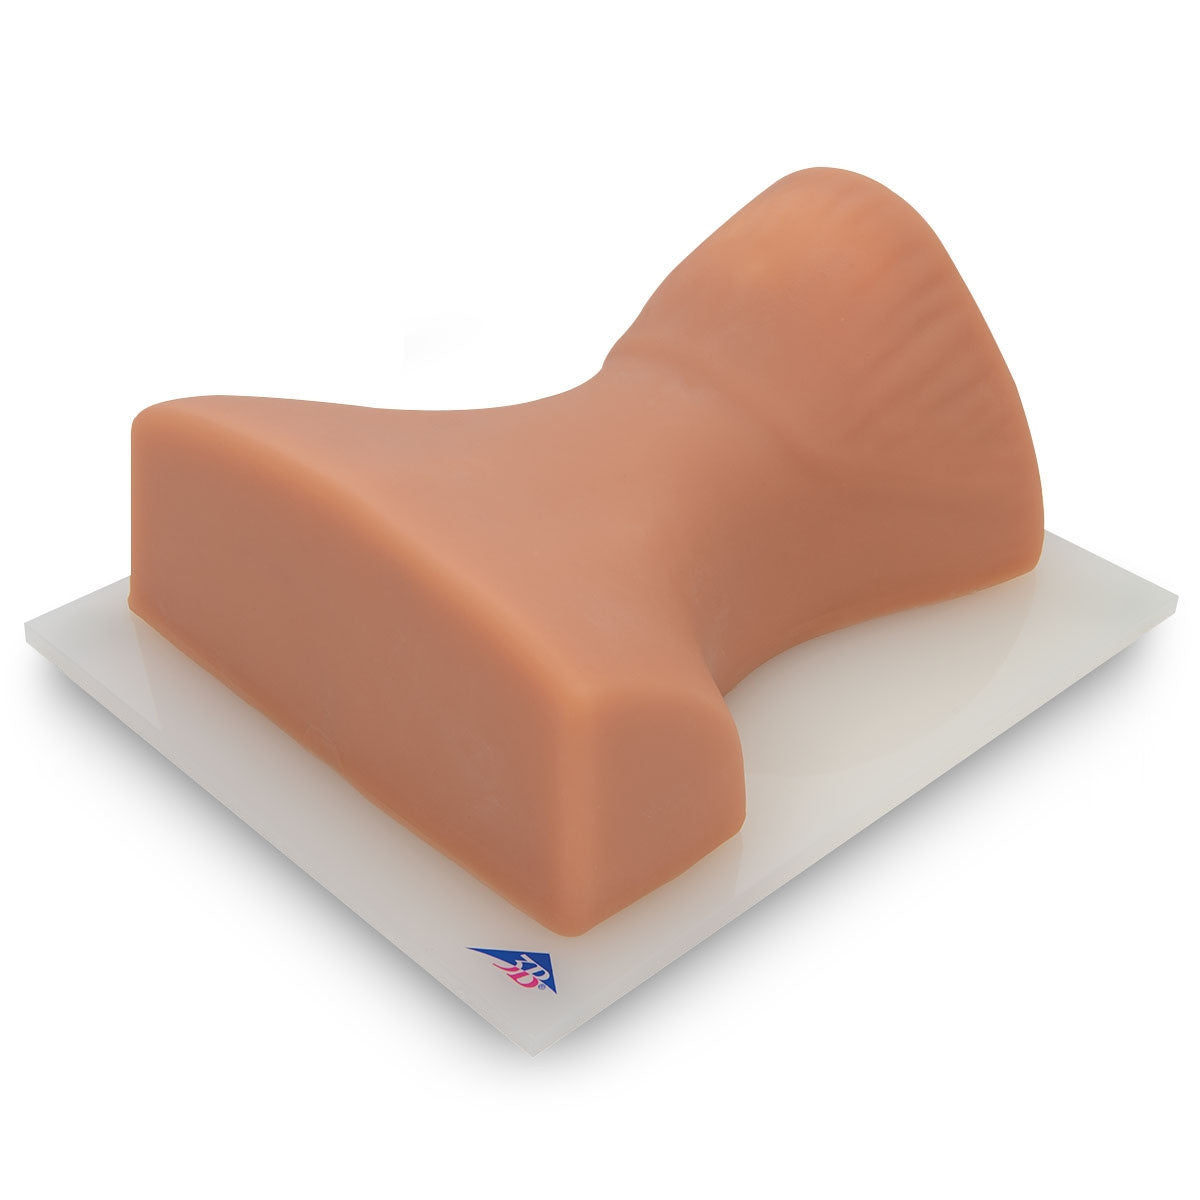

Epidural Injection Trainers

Train students and healthcare professionals in essential epidural injection skills using our highly realistic spine simulators, designed to enhance clinical training and procedural accuracy.

Replacement Skin for Epidural and Spinal Injection Trainer

Our range of epidural injection trainers includes detailed anatomical models that replicate the lumbar and thoracic spine, providing a hands-on learning experience for anaesthetists, medical students, and pain management specialists. These advanced simulators allow users to practise needle placement, identify key anatomical landmarks, and develop proficiency in administering epidural and spinal anaesthesia with confidence. Ideal for medical schools, hospitals, and professional training programmes, these epidural trainers support skill development in regional anaesthesia, labour pain management, and spinal procedures. With lifelike materials that simulate real patient responses, our models offer a realistic and immersive training experience.